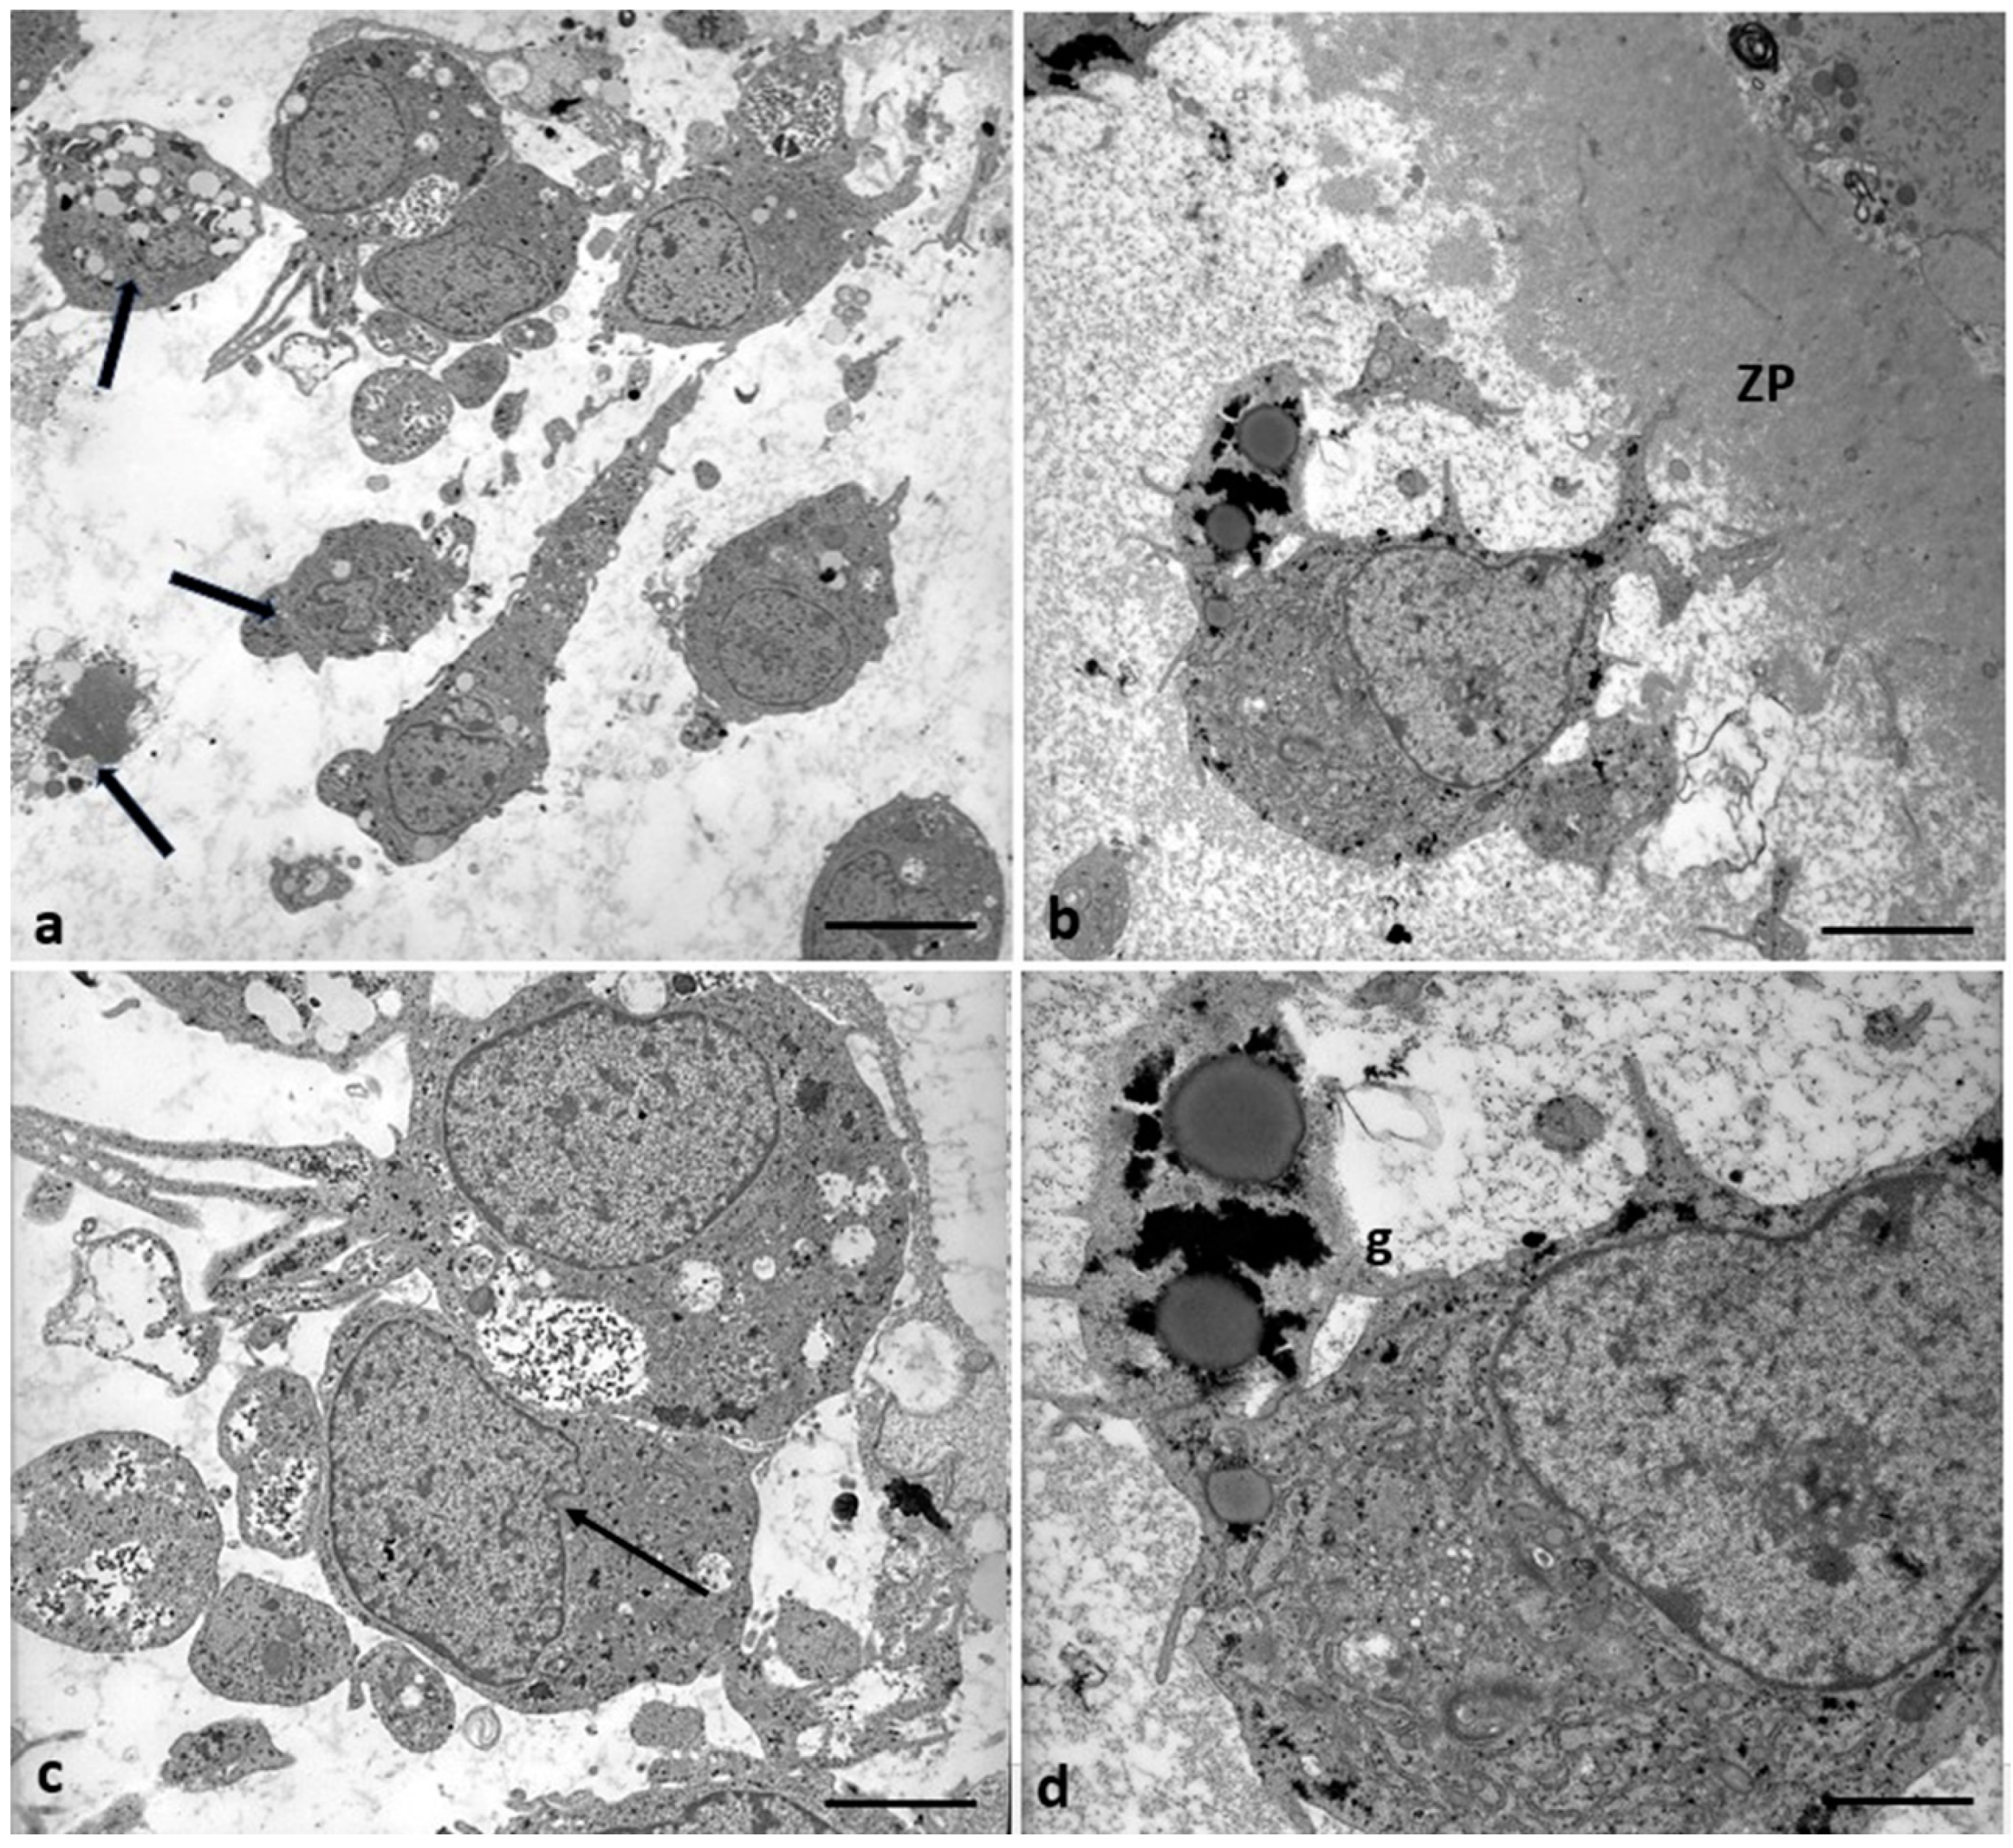

In 71.4% of the Group 2 patients (5/7), the CCs appear with moderate electron density, dispersed within a fine and delicate fibrillar extracellular matrix, irregularly rounded, polyhedral, or elongated in shape (Figure 9a), with large and short cytoplasmic processes projecting through the ZP that did not seem to reach and contact oocyte microvilli (Figure 9b). The shape of nuclei changed from oval to flattened and indented (Figure 9c, thin arrow, and Figure 10b), and abundant glycogen granules were detected, dispersed in the cytoplasm, and around numerous and large lipid droplets. Micro-peroxisomes, organelles that confer the steroidogenic ability to these cells, have not been observed.

Figure 9.

Morphological changes in the shape of CCs of Group 2 patients. (a) CCs dispersed within the extracellular matrix, with a shape irregularly rounded, polyhedral, or elongated, and some cells showing characteristic signs of apoptosis (thick arrows). (b) CCs with large cytoplasmic processes projected in the ZP. (c) cell nuclei appear flattened and indented (thin arrows), and (d) abundant granules (g) of glycogen appear dispersed in the cytoplasm, around lipid droplets, and inside vacuoles. Bar = 180 µm (a); Bar = 90 µm (b); Bar = 70 µm (c); Bar = 40 µm (d).

In 28.6% of the Group 2 patients (2/7), CCs showed even characteristic apoptotic signs (Figure 9a, tick arrows, and Figure 11).

Figure 10 highlights details of the presence of abundant glycogen granules in the CCs of Group 2 patients. They were distributed particularly in the cytoplasm, close to nuclear indentations (Figure 10a,b, arrows), around lipid droplets (Figure 10c,d), which indicates a possible impairment of the metabolism of carbohydrates and glucose homeostasis.

Figure 11 shows degenerating CCs in Group 2 patients. Numerous regressing elements such as vacuoles of different sizes and autophagosomes containing glycogen granules and involuting mitochondria are present (Figure 11a–c); cytoplasmic fragments deriving from cellular blebbing (Figure 11c), pyknotic (Figure 11c) or regressing nuclei (Figure 11a–c), and a dense or lysed, vacuolized cytoplasm (Figure 11d) were observed.